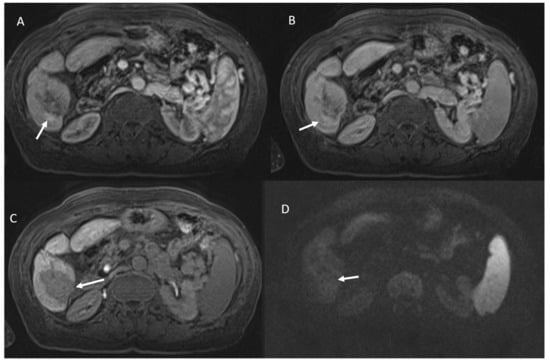

- 53 showed non rim APHE and 60 hypointense SI during arterial phase (Figure 5).

- 3 showed peripheral washout appearance and 110 hypointense SI in portal phase (Figure 5).

- 113 lesions were hypointense in equilibrium phase.

- 98 showed iso-hypointense SI in T2-W and 15 iso-hyperintense SI in T2-W (Figure 6).

- 100 showed hyperintense SI in T1-W and 113 targetoid appearance.

- 84 lesions showed restricted diffusion (Figure 7) with iso-hypointense in ADC map and 29 showed no restricted diffusion.